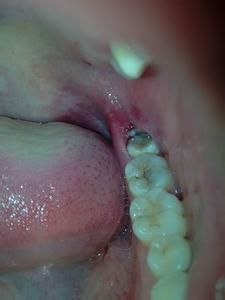

3.空間不足引起冠周炎症:智齒在人類的演化史上,是屬於消逝狀態。因此牙弓也越來越小,空間不足的情況是很常見的。萌出時患者會有腫脹、疼痛感。為了避免此種情況再次發生,建議在炎症消退後儘快到醫院拔除。

(1)反覆發作的冠周炎。阻生的智齒牙冠周圍軟組織與牙齒之間形成一盲袋,引起食物、細菌的積存,抵抗力下降時,出現冠周炎是必然的。一般的消炎治療治標不治本,因此冠周炎會反覆發作。